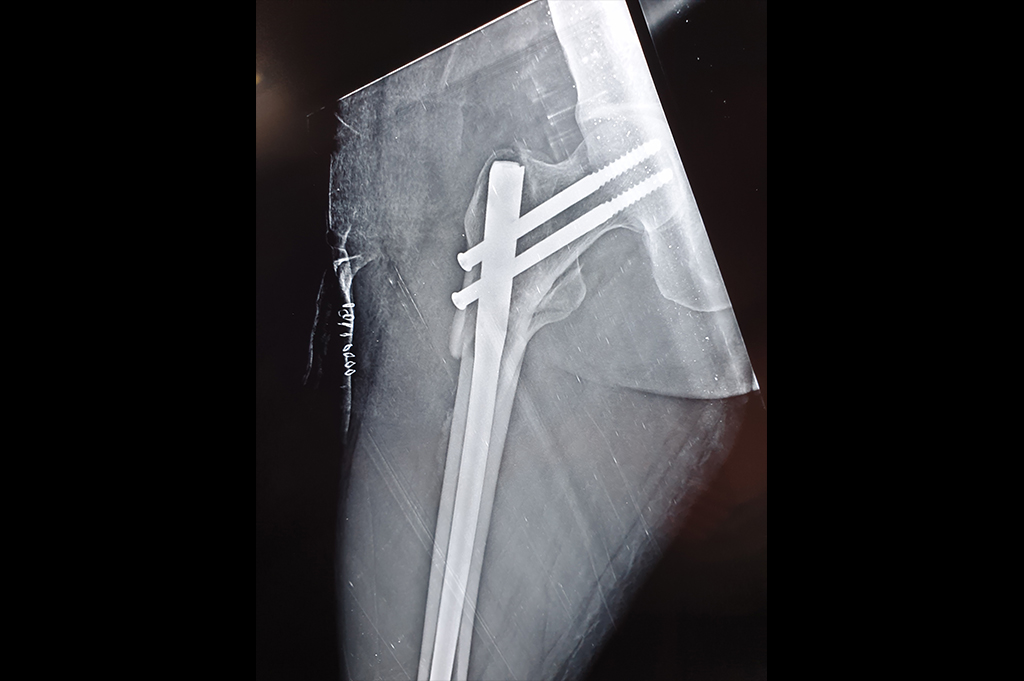

Intertrochanteric Fracture

Subtrochanteric Fracture